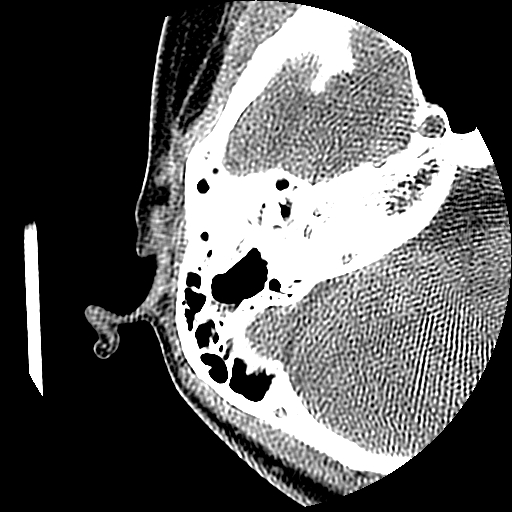

以下是引用随光逐影在2009-8-19 7:25:00的发言:[br]右侧慢性中耳乳突炎,右侧中耳腔及外耳道肉芽肿或胆脂瘤形成。